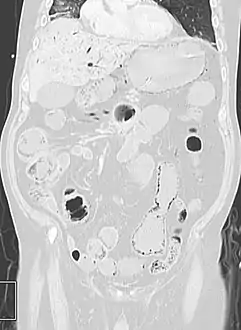

Pneumatosis intestinalis at computed tomography in intestinal ischemia. Lung window for better representation of the gas deposits in the intestinal walls. Coronal reconstruction.